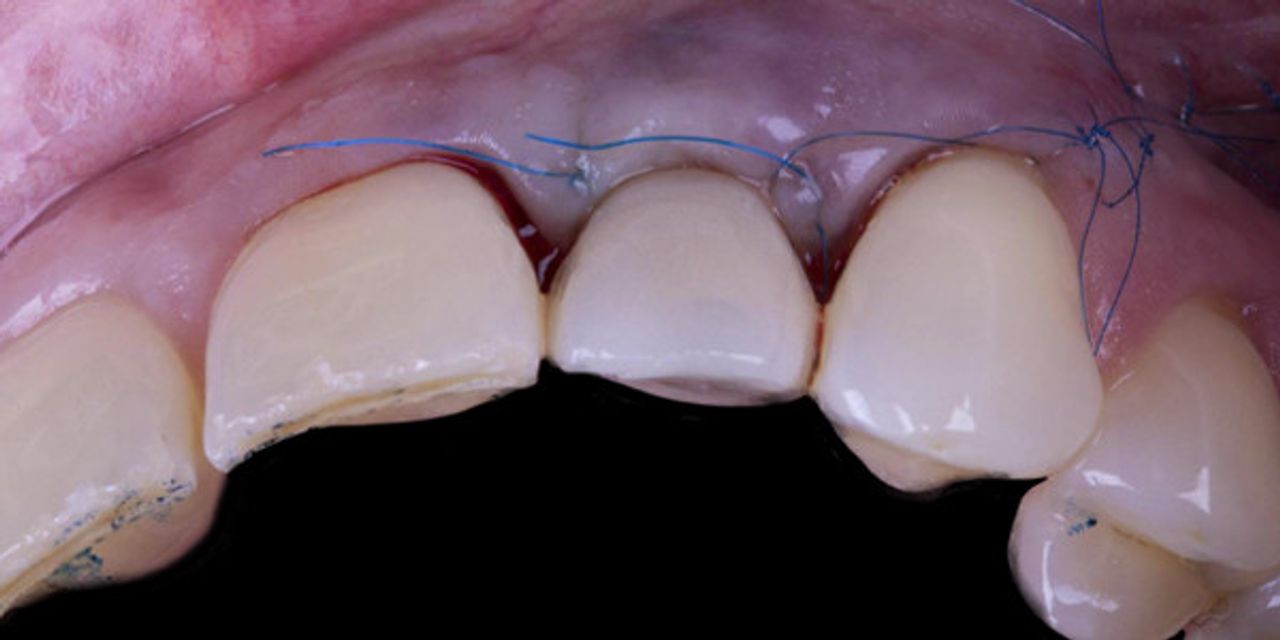

- Bundle and alveolar bone;- The role of keratinized tissue versus soft tissue thickness;- Mucogingival surgery for soft tissue dehiscence coverage around implants;- Mucogingival approach in combination with immediate post extraction implant placement and immediate loading;- Soft tissue augmentation and simultaneous guided implant placement in the aesthetic zone;- The soft tissue approach for implant installation after tooth extaction for periodontal reason;- Soft tissue augmentation procedures in edentulous areas before implant rehabilitation;- Step by step protocol of the split-full-split elevation technique to obtain coronal advancement of the flap;- Step by step protocol of connective tissue graft harvesting technique;- Step by step protocol of the “connective tissue platform technique” for soft tissue augmentation.